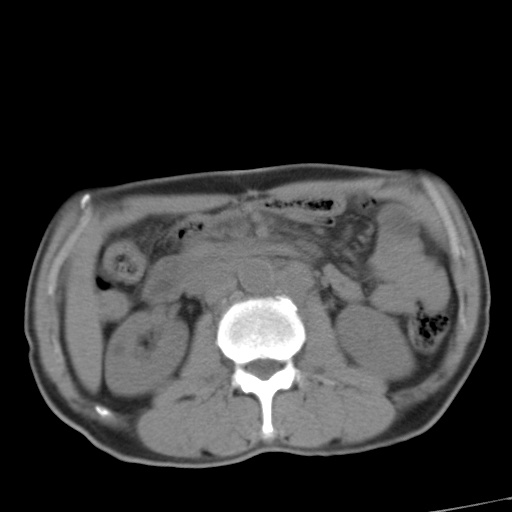

标题: CT17975:请求会诊。男、57岁。上腹部胀痛2天。临床诊断:糜 [打印本页]

标题: CT17975:请求会诊。男、57岁。上腹部胀痛2天。临床诊断:糜

肝脏多发类圆形低密度影,考虑肝脏转移瘤,肝胃韧带一淋巴结肿大,原发?胃癌?

考虑胃癌并肝脏及腹膜后淋巴结转移;不排除淋巴瘤。

肝内转移瘤,腹腔及腹膜后淋巴结转移。